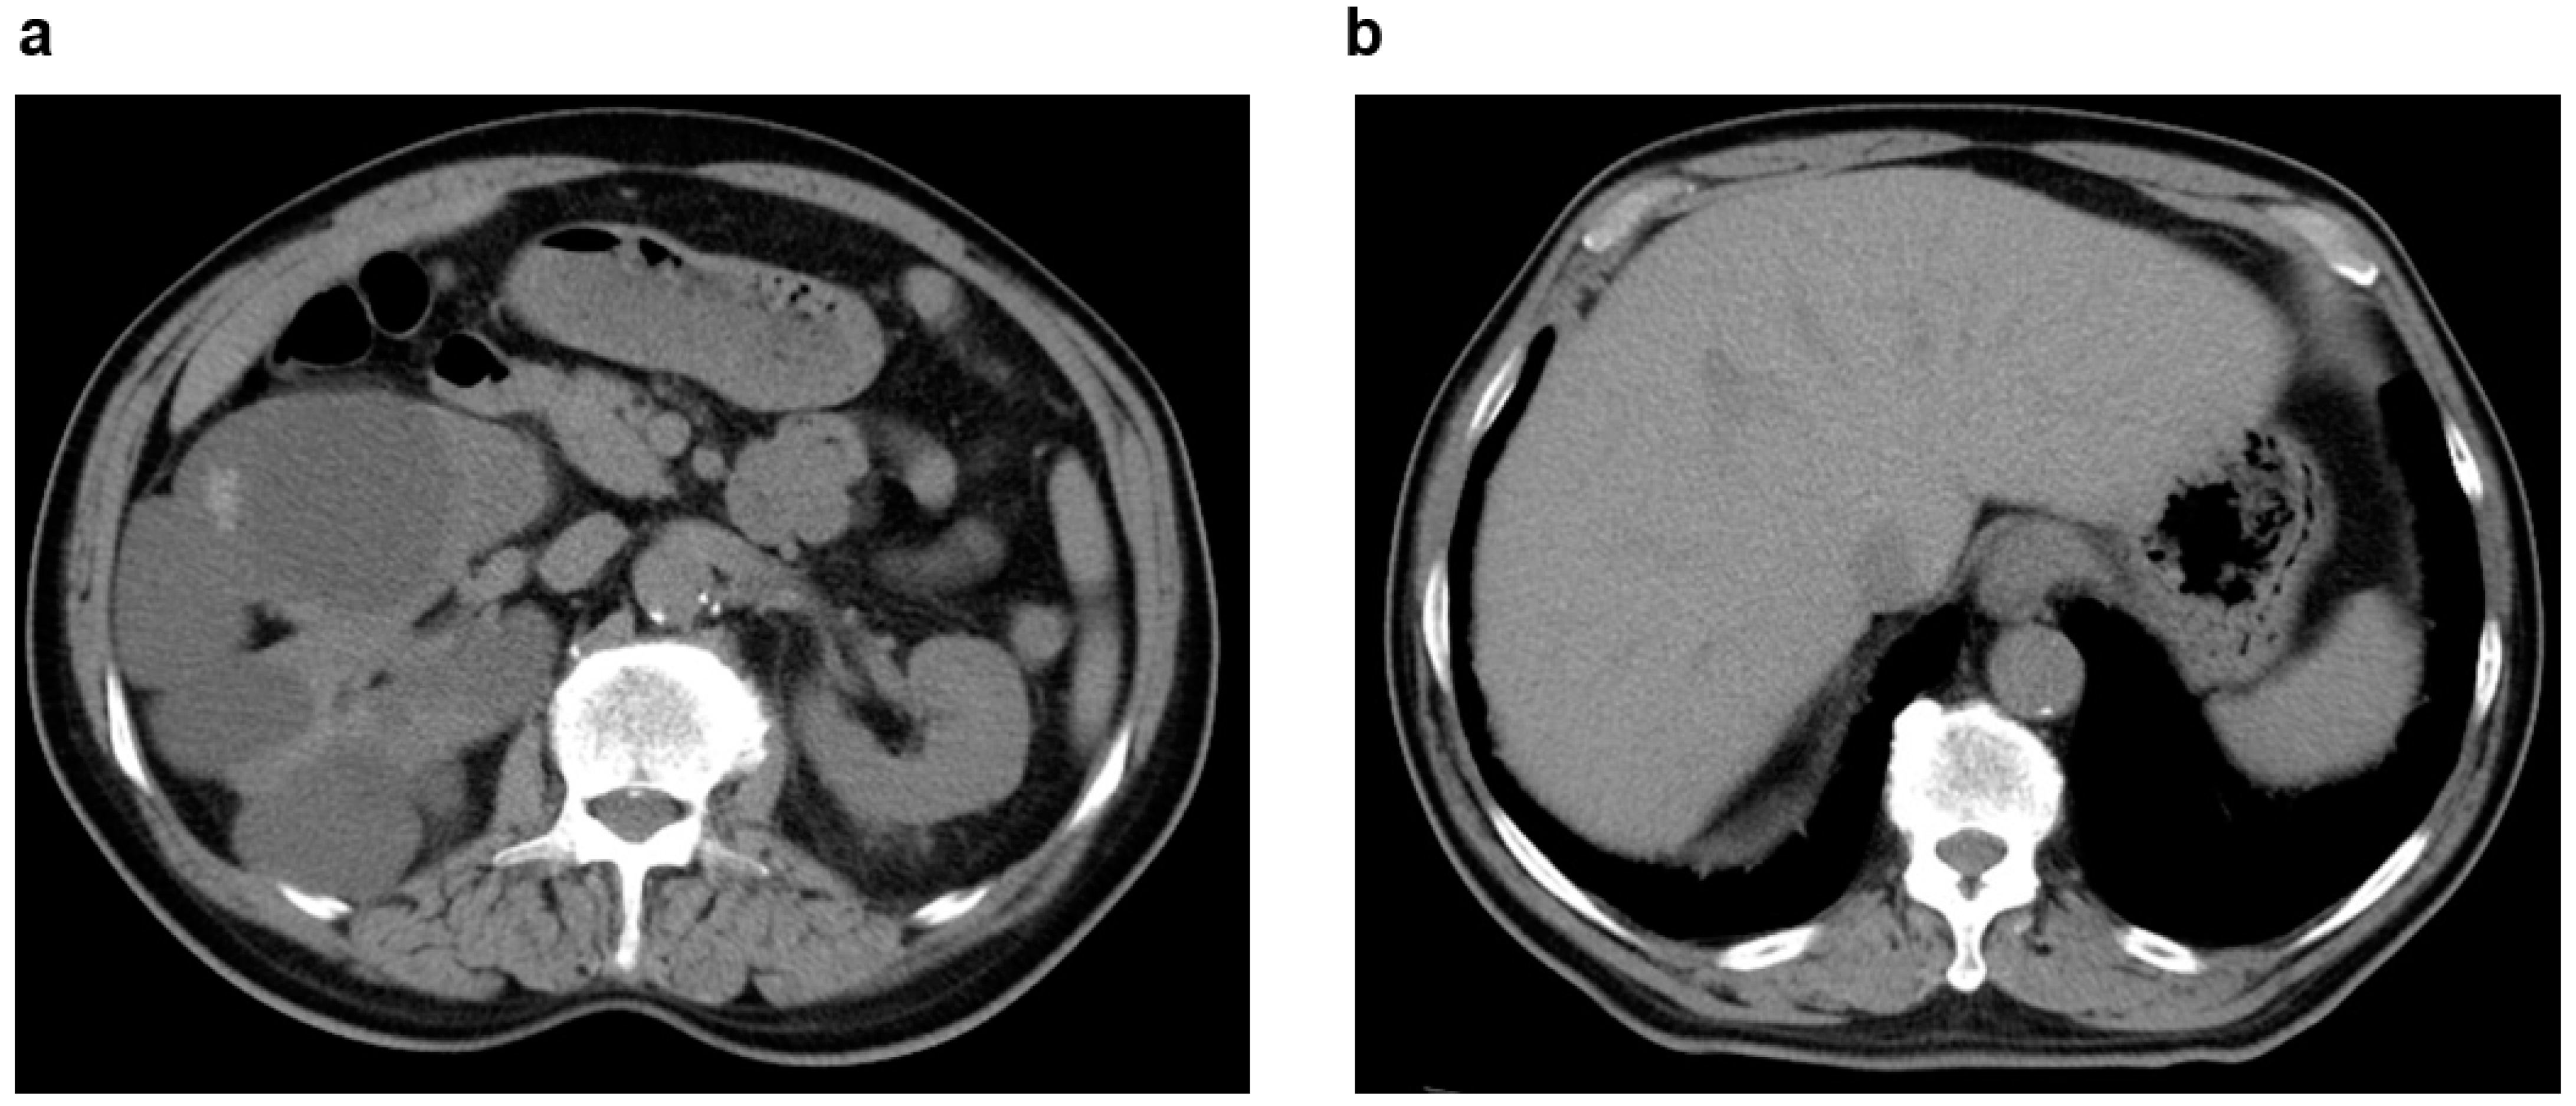

2.2. Acquired Cystic Kidney Disease (ACKD)

| ACKD | Common | In long-term dialysis patients, the renal parenchyma in both kidneys may show atrophy and proliferation of microcysts. Asymptomatic, but screening for hemorrhage and renal cancer development is necessary. | ||